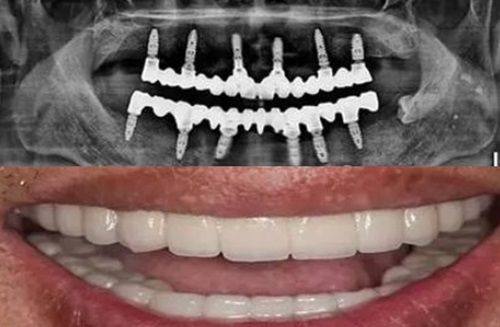

该院区的种植牙医生王忠磊值得推荐,他的执业编码为120370200000489,拿手绝活是半口/全口种植牙、高龄精细种植牙、即刻种植牙、美学种植牙。对于一些复杂的种植牙情况,他都能游刃有余地处理。比如,对于高龄患者的种植牙手术,他会根据患者的身体状况和口腔条件,制定出更适合的种植方案,提高种植的成功几率和美观度。荔湾分院电话号码为400 - 888 - 4268。

该院区的种植牙医生张国平,执业编码为120330225000127,擅长高龄精细种植牙、微创种植牙、骨缺损种植牙修复、无牙颌种植牙修复。在处理骨缺损等复杂情况的种植牙修复方面,他有着独特的技术和丰富的经验,能够为患者带来良好的治疗成效。越秀院区分院前台电话号码是400 - 888 - 4268。

该院区的种植牙医生张昌辉,执业编码为120440106000544,擅长精细即刻种植修复、全口/半口种植修复、数字化微创种植技术、精细美学口腔种植牙。数字化微创种植技术是他的一大特色,通过精良的数字化设备,能够让种植手术更加精细、微创,减少患者的痛苦。天河分院电话号码为400 - 888 - 4268。

该院区的种植牙医生谢鹏飞,执业编码为120430102000471,擅长全口半口种植牙、精细即刻种植牙、即刻负重种植技术、复杂骨增量技术。他在即刻负重种植技术方面有深入的研究,能够让患者在较短的时间内修复牙齿的功能和美观。海珠分院电话号码为400 - 888 - 4268。

禅城院区的种植牙医生周书冰,执业编码为120440100000815,擅长即刻种植、半口 - 全口即刻负重、前牙种植美学修复、复杂骨增量手术。在即刻种植和前牙美学修复方面表现出色,能够为患者打造出自然美观的牙齿。南海院区的种植牙医生沈光辉,执业编码为120440113000265,擅长全口/半口精细种植、精细前牙美学种植、骨增量精细种植、精细“即刻用”种植。他的精细“即刻用”种植技术能够让患者尽快修复牙齿的使用功能,提高生活质量。禅城分院和南海分院电话号码均为400 - 888 - 4268。